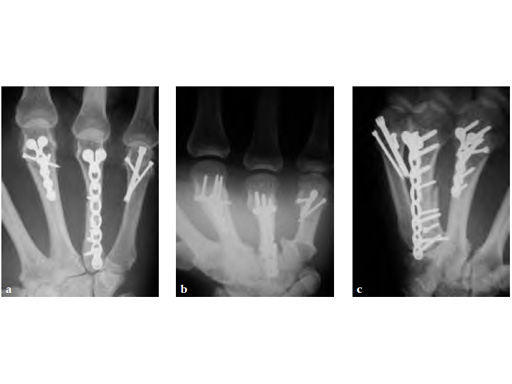

Periarticular complex metacarpal fracture treated with 1.5 LCP modular hand system and 1.5 headless compression screw.

Fig 1 Preoperative.

Fig 2ac Postoperative.

Case provided by Tom Fischer, Indianapolis, USA